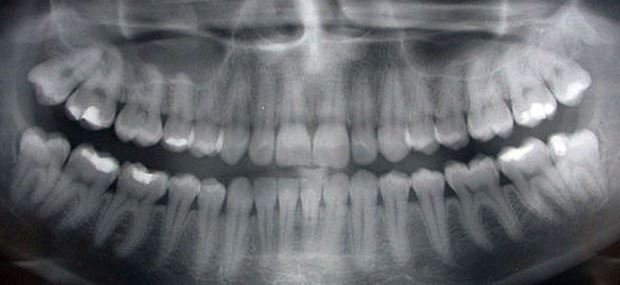

Röntgen ist aus der Zahnmedizin nach wie vor nicht wegzudenken. Mittels Röntgenstrahlen lassen sich äußerlich nicht sichtbare Strukturen, Erkrankungen oder für bestimmte Eingriffe problematische Wurzelverläufe feststellen und entsprechende Behandlungsschritte einleiten. Bei dieser Diagnosetechnik macht man sich die Eigenschaft der Röntgenstrahlen zu Nutze, verschiedene Körperbestandteile und Gewebe unterschiedlich stark zu durchdringen. Die Strahlen treffen anschließend in unterschiedlicher Stärke auf ein belichtungsfähiges Filmmaterial auf und bilden die durchstrahlten Körperregionen ab.

Durch Einzelzahnaufnahmen erstellt der Zahnarzt detaillierte Bilder einzelner Zähne und seiner Nachbarzähne. Das gesamte Gebiss kann zum Beispiel mithilfe des Panoramaröntgengerätes (Orthopantomograph, OPG) aufgenommen werden. Für die Karieserkennung im Zahnzwischenraum bieten sich so genannte Bissflügelaufnahmen an.

Die Weiterentwicklung im medizintechnischen Bereich hat das digitale Röntgen hervorgebracht. Dabei wandelt ein Sensor die absorbierten Röntgenstrahlen in digitale Signale um und macht sie am Computerbildschirm sichtbar.